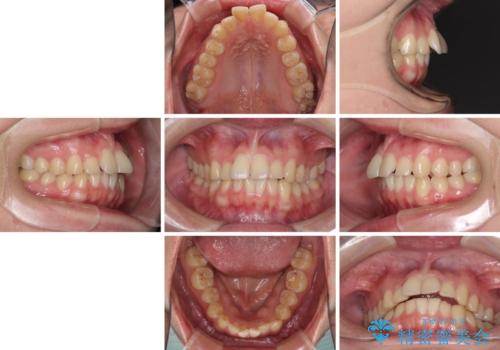

- 食いしばりが気になっていたとのことで来院された患者様です。

当初は睡眠時のマウスピースのみの製作をご希望でしたが、矯正治療の提案をしたところ、インビザラインにて矯正治療を行うこととなりました。

矯正治療中に食いしばりがより強くなることがあるため、半年に1回のペースでボツリヌストキシンによる咬合力緩和を並行して行うこととしました。

咬合力の緩和と食いしばりがちな咬み合わせが改善され、顎の負担が大幅に軽減されました。